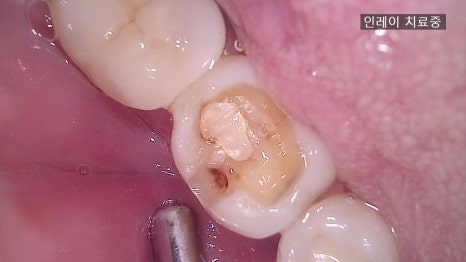

① Removal of decay and tooth reduction

– The decayed area is removed and the space for the inlay is carefully shaped with precision.

② Intraoral scan

– The tooth shape is digitally captured with an intraoral scanner. (More accurate and faster than traditional impressions.)